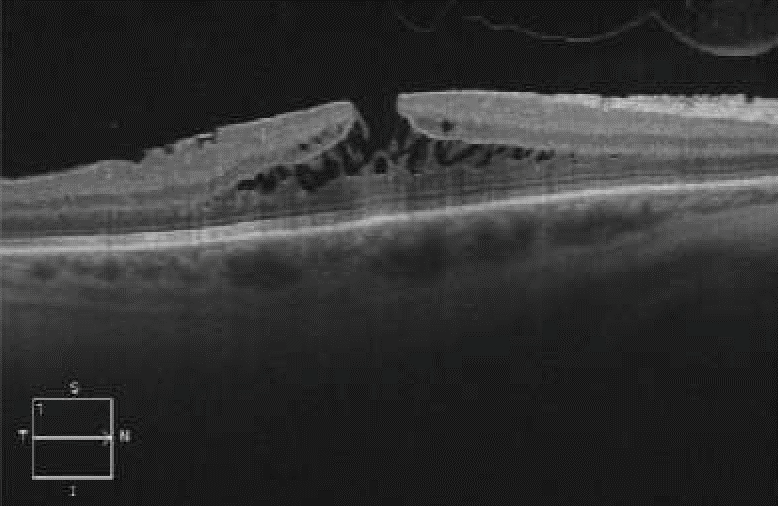

Case of epiretinal membrane foveoschisis (ERMF). Can be recognized by the presence of foveoschisis in the outer retinal layers (between the outer plexiform and the outer nuclear layer). A hyperreflective contractile epiretinal membrane can also be observed.

| current | 21:07, January 5, 2024 | 778 × 506 (99 KB) | Mélanie.Hébert (talk | contribs) | Case of epiretinal membrane foveoschisis (ERMF). Can be recognized by the presence of foveoschisis in the outer retinal layers (between the outer plexiform and the outer nuclear layer) (star). A hyperreflective contractile epiretinal membrane (white arrows) can also be observed. |